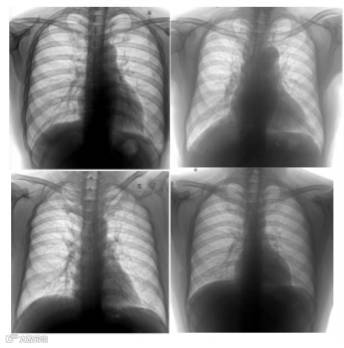

应用示例:智能放射影像分析--检测肺部增厚症状

正如现阶段,对于各地区中小医院和社区医院来说,症状并不明显的疾病还是很难进行准确检测。但通过认知系统,从历史数据中学习和总结,快速判读影像中的病症特征,辅助医生进行病症分析,从而提高诊治效率和准确性。 如图中肺部影像分析示例,该方案可以告诉医生此X光片的患者有多大的概率患有“肺部增厚”病症,医生可以据此做出自己的判断,避免漏诊、误诊,提升效率。